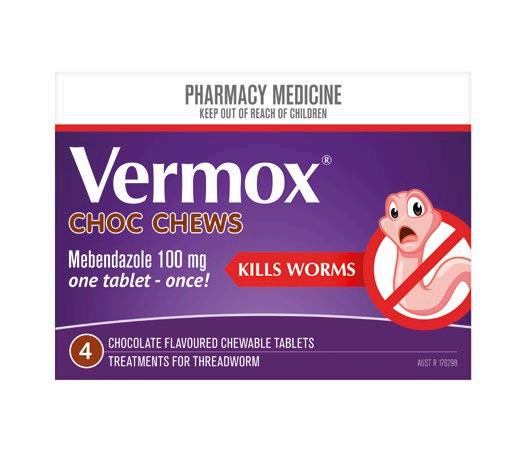

Eliminates intestinal threadworm with one single-dose tablet Chocolate flavoured chewable tablets Available in packs of 2, 4, 6 and new 10 Tablet Family Pack Soothes the throat Contains Manuka honey Supports immune heath Blended with Wellmune® for immune health support and natural New Zealand Manuka honey to coat the throat. Bursting with delicious and soothing flavours. Effective worm treatment Soothe dry, tickly throats De-Worm Extra Strength 500mg 2 Tabs $699 4 Tabs $999 6 Tabs $1199 $1399 Multichem NZ Ltd, Auckland $699 20 Tabs Radiant Health Ltd, Auckland Pharmac y only me dicine O ne t ablet once for any memb er of the family 2 year s and over Radiant H ealth Ltd , Auckland SEE F ULL RANGE I N S T O R E GREAT CHOCOLATE FLAVOUR KI LL S WO RM S ONE TABLET ONCE Vermox Choc Chews 4 pack $1399 De-Worm Extra Strength 500mg Family Pack 10 Tabs Offers and advertised products may not be available at all participating pharmacies. Offers are valid from Monday 6 March to Friday 24 March 2023 or while stocks last. Prices printed in this brochure are Recommended Retail Prices (RRP). Always read the label. Use only as directed. If symptoms persist see your doctor or health professional. Vitamins are supplementary to a balanced diet. Full product information is available from your pharmacy TAPS PP9728. BACK TO SCHOOL ESSENTIALS